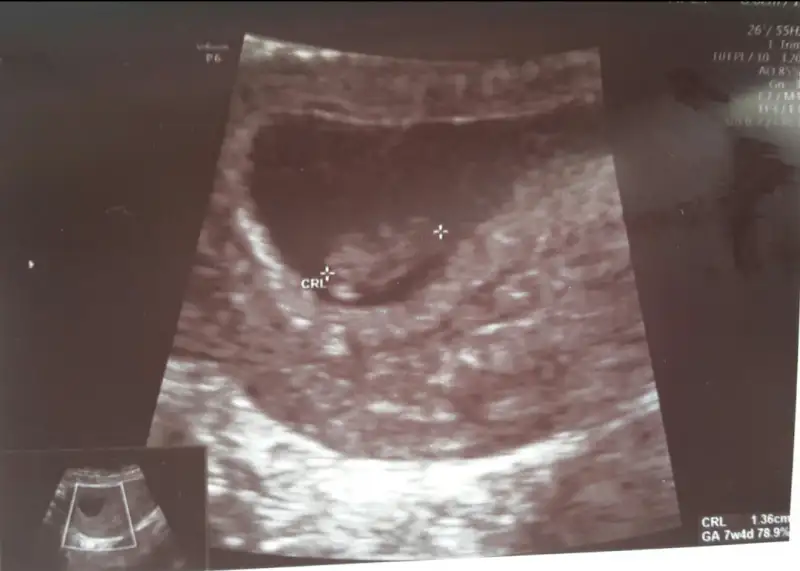

Bence kız gibi: )Kızlar yorumlarınızı rica ediyorum :) karından değil vajinal.

Bence erkek gibiKızlar karından usg bi bakabilir myiz